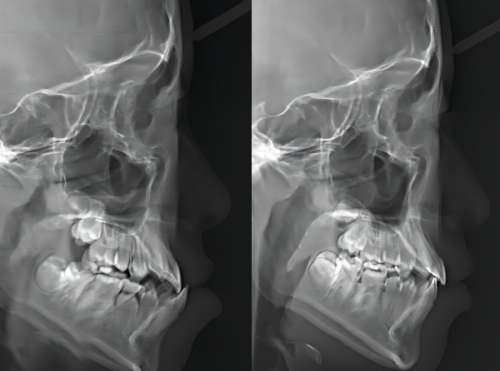

贵阳拜尔口腔门诊部配备了新型的口腔医疗设备,这些设备能够确保诊疗的精细度和效率。 其中,芬兰Planmeca ProMax口腔全景X射线机能够完善、清晰地展示患者的口腔状况,为医生制定诊疗方案提供有力支持。Planmeca ProMax 3D Mid口腔CT则可实现三维重建,直观展示口腔结构,为复杂手术进行精细定位。 进口瑞士超声洁牙机、喷砂洁牙机能够有效去除牙结石、牙菌斑等污垢,让患者的牙齿修复洁白健康。智能化种植牙、智能化美学正畸、智能化牙齿修复系统则实现了牙科3D智能化全景口腔体检,能够为患者提供个性化的治疗方案。